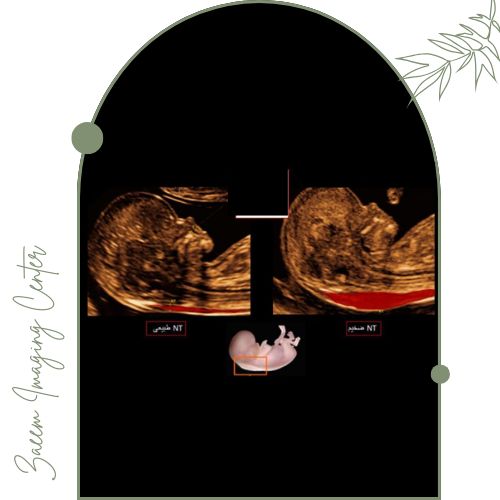

در این مرکز از دستگاههای پیشرفته سونوگرافی ویژه NT استفاده میشود. این تجهیزات تصویری کاملاً واضح از ضخامت شفاف پشت گردن جنین (NT) و سایر شاخصهای مهم سلامت جنین بهدست میدهند که نقش کلیدی در تشخیص سریع و دقیق اختلالات ژنتیکی دارند.اطلاعات جمعآوری شده توسط متخصصان با بالاترین استانداردها تحلیل و گزارش میشود تا مادران با اطمینان روند بارداری را طی کنند.